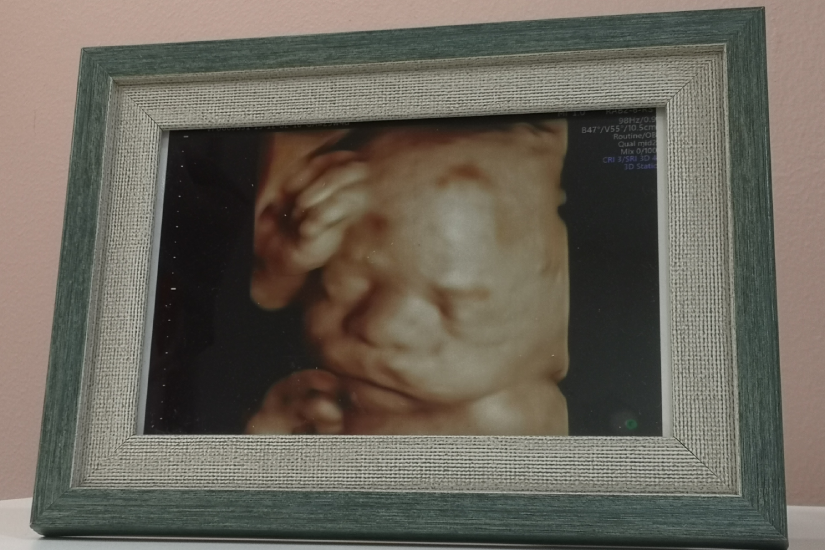

Ecografia 3D și 4D reprezintă tehnologii avansate de imagistică utilizate în timpul sarcinii pentru a oferi imagini detaliate ale fătului. Ecografia 3D utilizează ultrasunetele pentru a crea imagini tridimensionale ale fătului. Astfel, se obține o imagine mai clară a structurilor anatomice fetale.

Ecografia 4D este o formă avansată de ecografie 3D, care adaugă elementul de timp, oferind imagini în mișcare în timp real. Practic, ecografia 4D creează un video al fătului în mișcare, permițând observarea expresiilor faciale și a activităților fetale în direct.

Comparativ cu ecografia clasică, 2D, cele două variante mai performante au avantajul că oferă imagini mai clare și mai detaliate ale fătului. Astfel, aceste forme de ecografie devin extrem de utile pentru a oferi viitorilor părinți o imagine a ce înseamna malformația fetală descoperită și evoluția acesteia.

Este important de menționat că imaginile detaliate furnizate de ecografiile 3D/4D pot ajuta medicii să planifice intervenții medicale prenatale sau postnatale necesare. Acestea oferă o înțelegere mai bună a problemelor medicale, astfel că simplifică procesul de diagnostic.

În plus, prin intermediul ecografiei 3D sau 4D, conexiunea dintre părinți și făt se consolidează. Este foarte important pentru părinți să-și vadă mai bine copilul, această procedură oferindu-le o oportunitate unică de a se conecta emoțional cu fătul lor înainte de naștere.